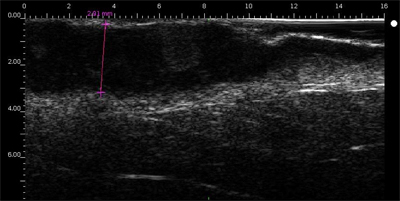

Echographie hypoéchogène, avec échos peu denses. L’écho d’entrée est peu marqué voire absent (absence de kératose, ulcération).

Mélanome ulcéré sur l’avant bras (épaisseur mesurée à 3.68 mm à l’échographie, épaisseur histologique).

Lésion infiltrant le derme.